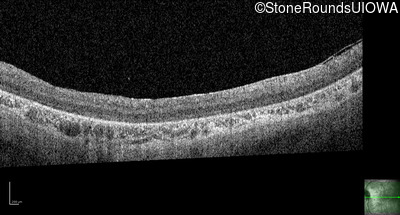

Optical Coherence Tomography - Left - 10/350 sc

Exemplar / OCT Stack